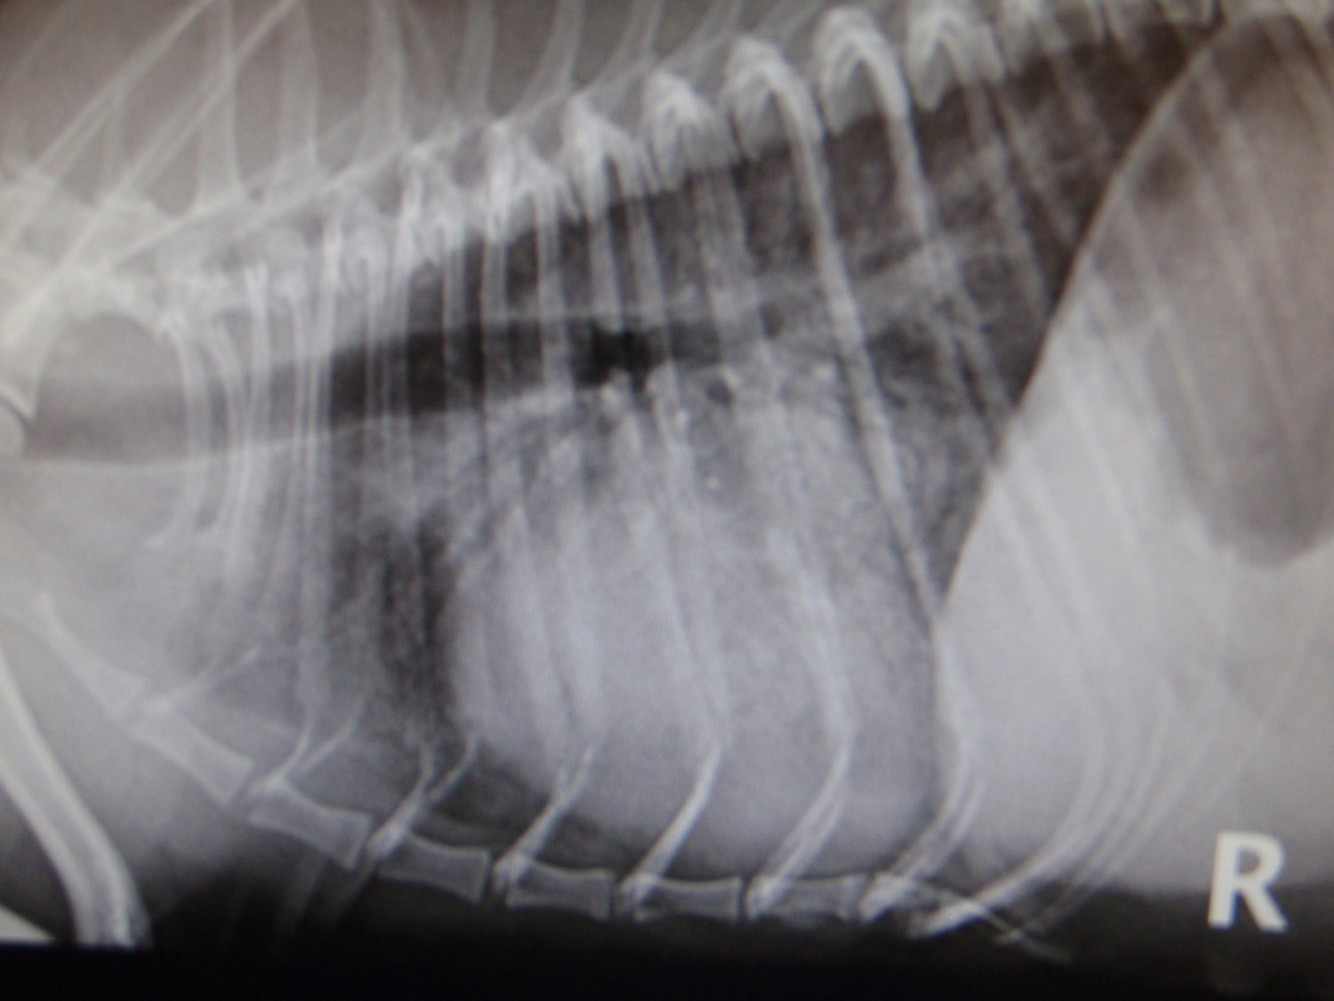

Describe what can be seen on this radiograph

Typical nodular thickenings, this is severe, advanced pathology – this valve wont be very effective as big gaps in it! As blood regurgitates to atrium as a result, we get damage to atrial wall and causes jet lesions which weaken the wall and this atrial wall may rupture